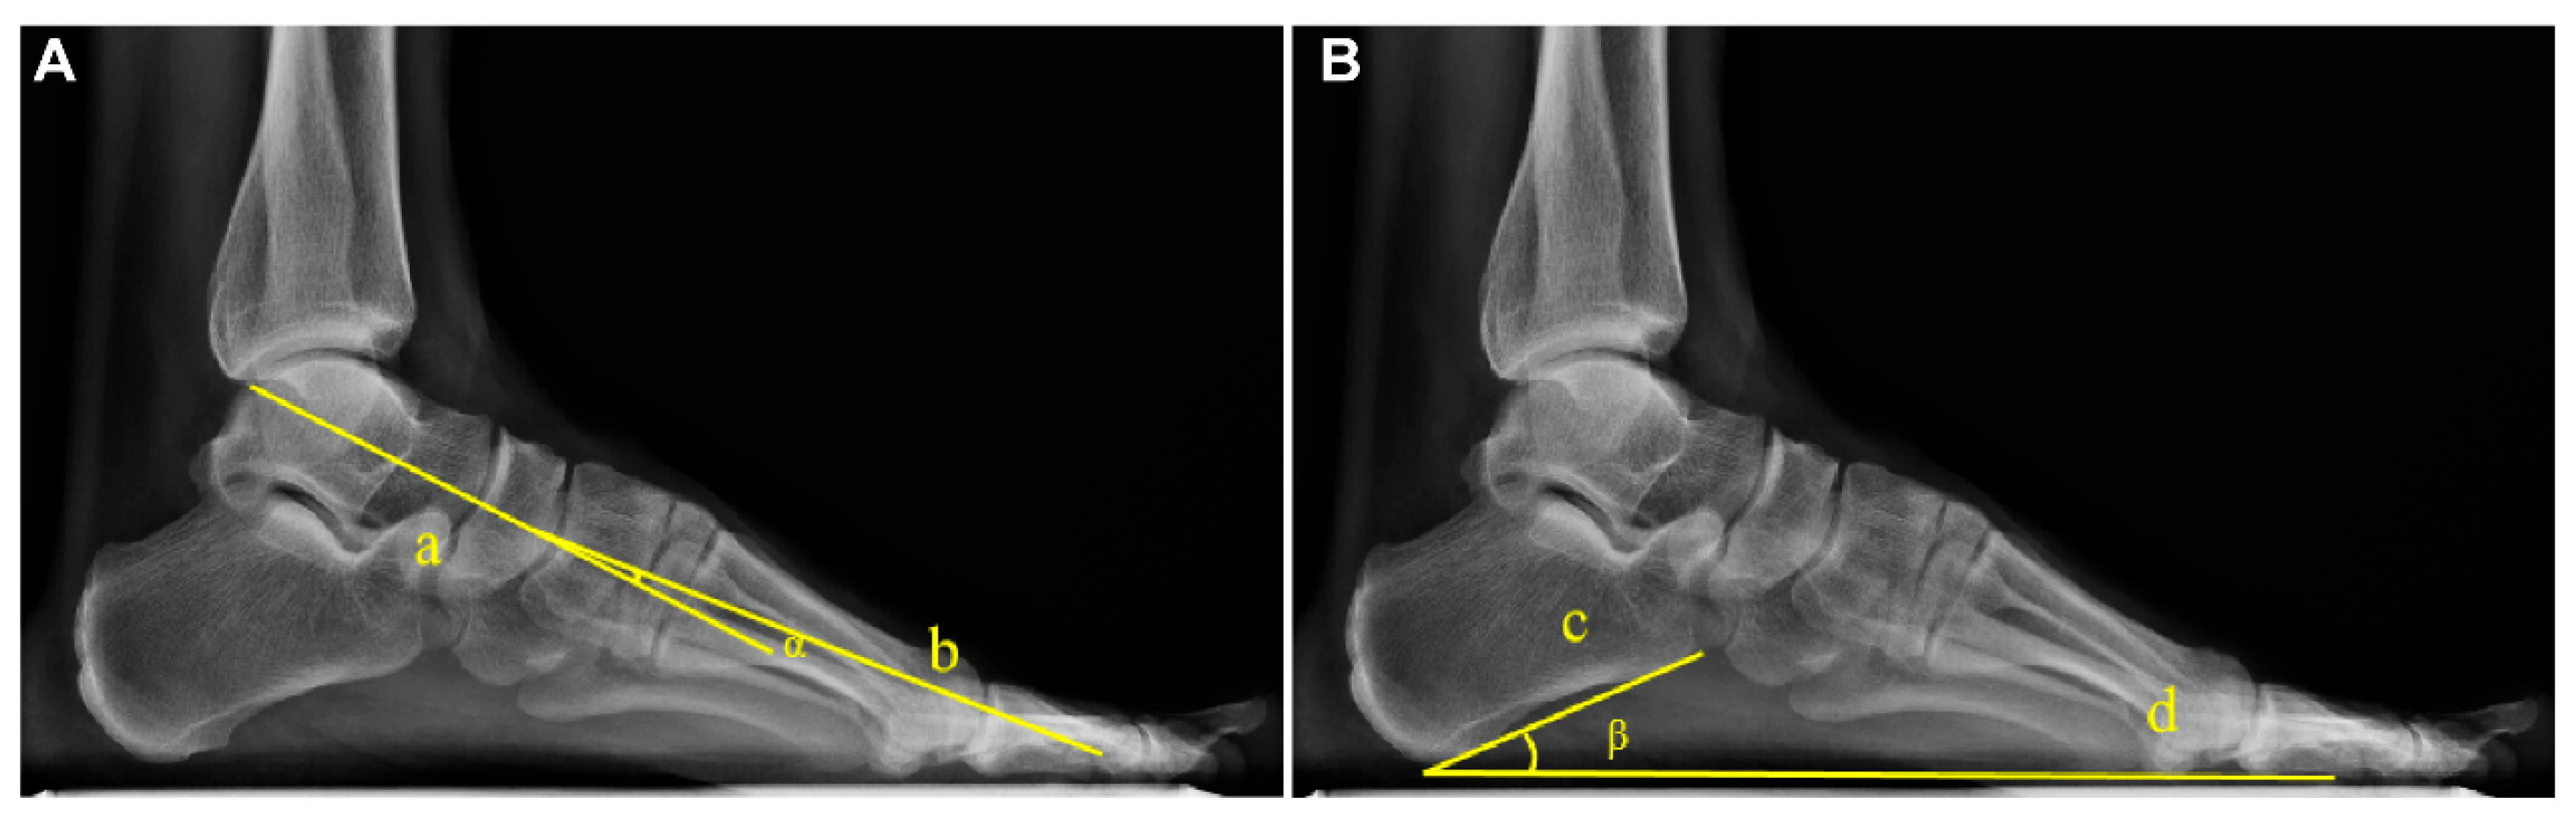

The Meary angle was measured as the angle between the longitudinal axis of the talus and the longitudinal axis of the first metatarsal, with a normal range of 0° ± 4° [11,18]. The Pitch angle was defined as the angle between the inferior border of the calcaneus and the horizontal line, with a normal range of 20–30°. The measurements are exemplified in Figure 1.

Figure 1.

Example diagram of arch angle measurement based on WB X-rays. (A) The Meary angle (α): formed by the longitudinal axis of the talus (Line a) and the longitudinal axis of the first metatarsal (Line b). (B) The Pitch angle (β): formed between the tangent to the inferior border of the calcaneus (Line c) and the line connecting the lowest point of the calcaneus to the lowest point of the medial sesamoid of the forefoot (Line d).

The diagnostic criteria for flatfoot in this study were defined as Meary angle > 4° or Pitch angle < 20° [11,18,19].